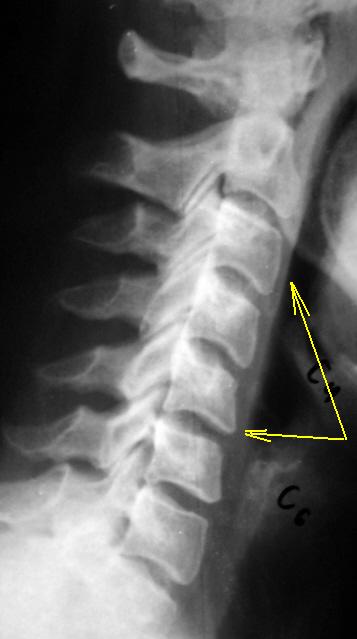

Да, налицо "сглаженность" шейного лордоза с тенденцией формирования кифоза - желтые стрелки, следовательно дискоз имеет место быть однозначно.

Да и остеохондроз уже также имеет место быть.

Выпрямление шейного лордоза с формированием кифоза. Остеохондроз ШОП, в виде скошенности передне-верхних углов тел С4-С6 с умеренным снижением высоты м/п дисков на этом уровне.Уверен,что и унковертебральный артроз будет в прямой проекции.